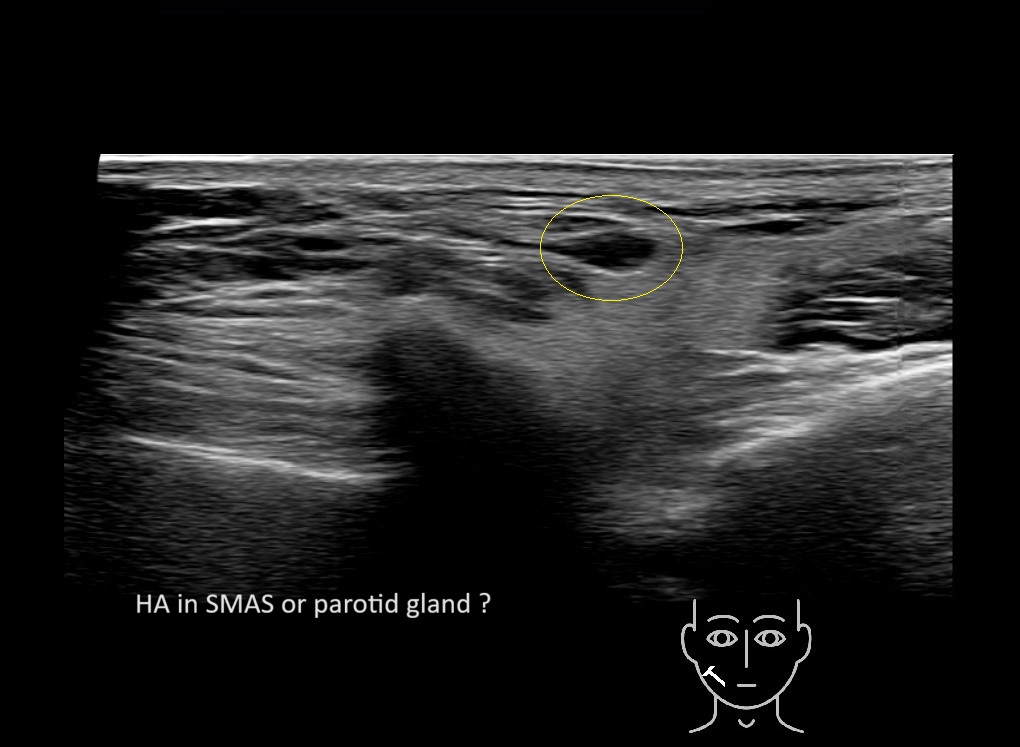

Parotid

Filler injections in the parotid gland may go unnoticed, however, inflammatory reactions and abscesses may occur. Hypervascularity can be seen with color doppler. Filler deposits are supposed to be injected into the superficial fatty layer . The space to inject into this layer may be limited. Routinely we measure a width of 2-4 millimeters with sometimes subcutaneous layers being less than one millimeter thick.

Study the first image to recognize the different layers. If you are sure about the layers, swipe to the second image to view the answer (if applicable).